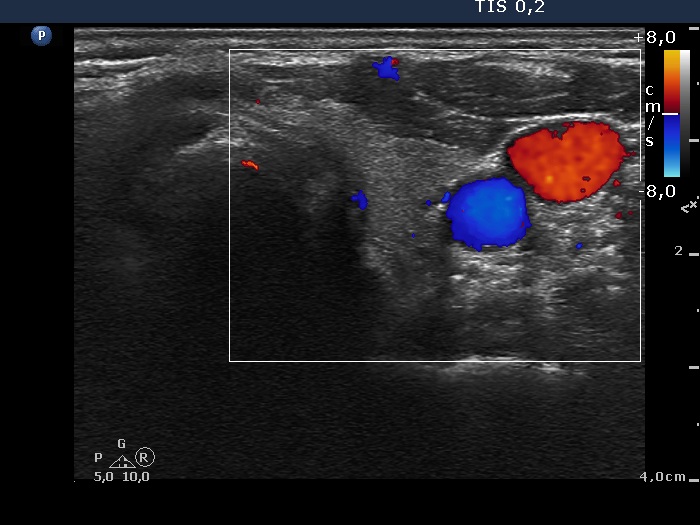

Right lobe, longitudinal scan

Left lobe, transverse view, color Doppler mode. This lobe is avascular.